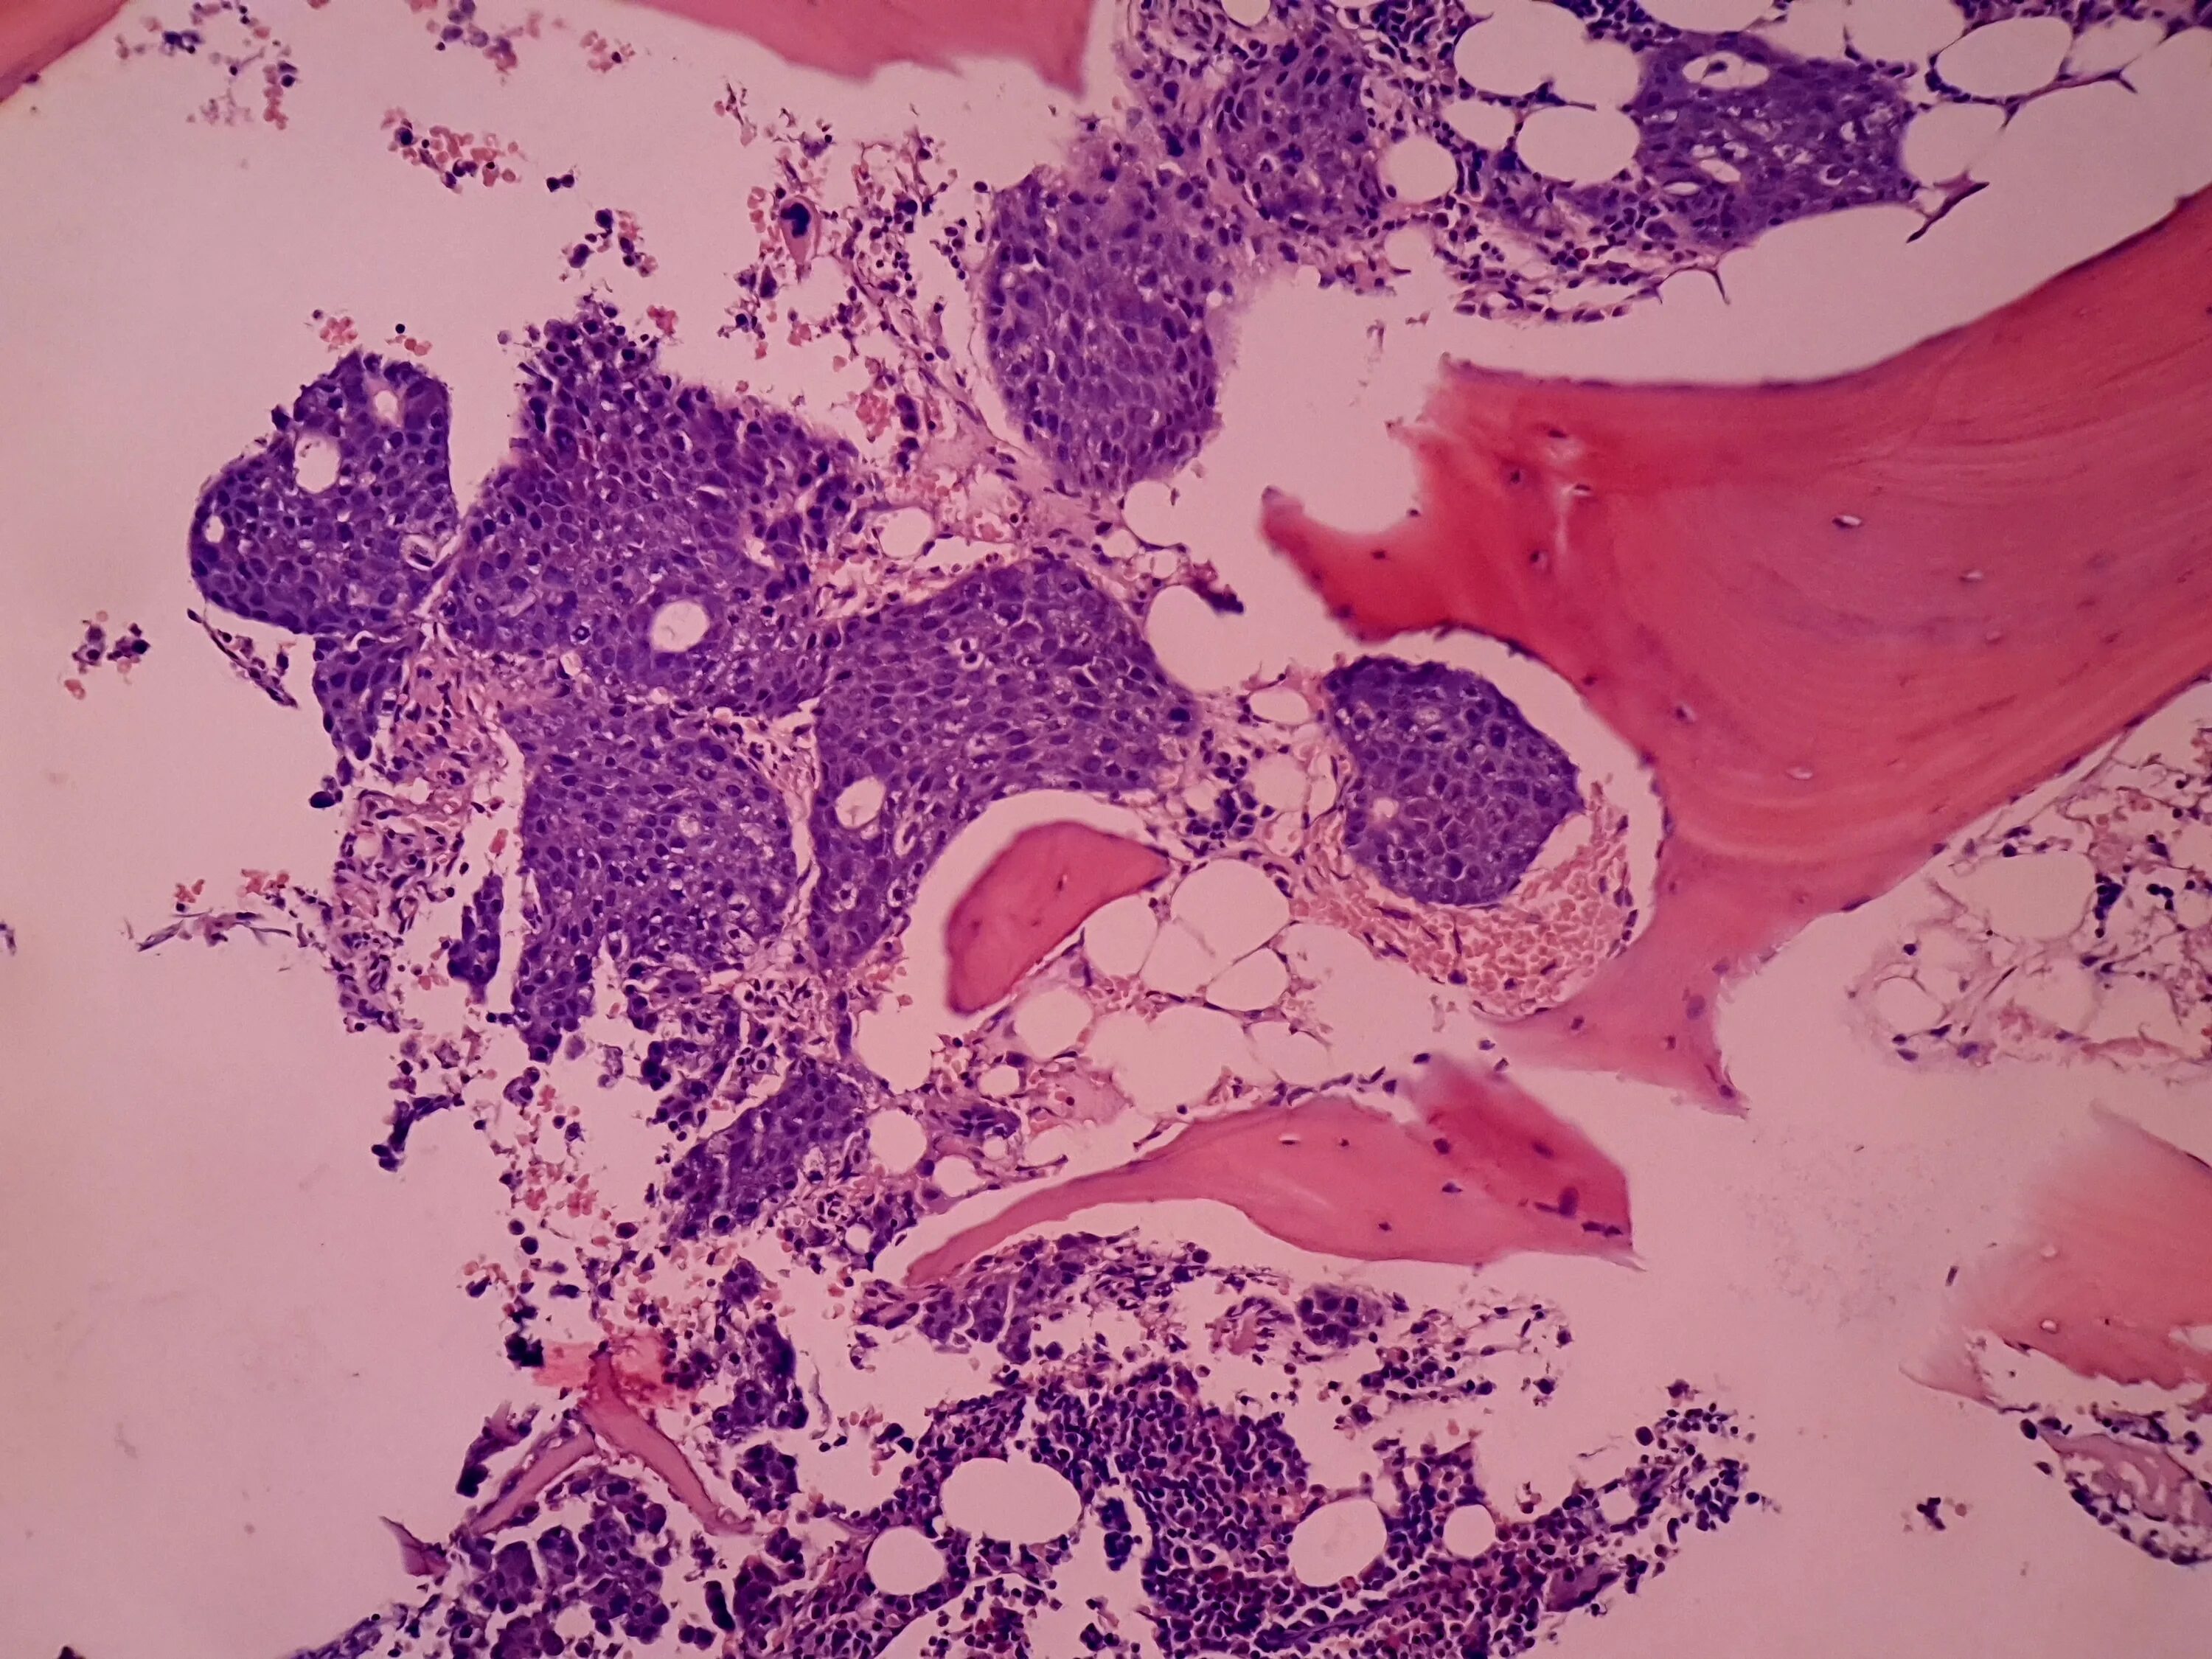

Metastasis